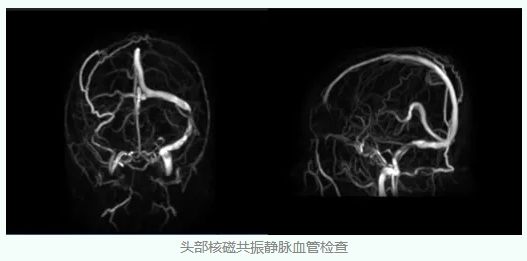

头部核磁共振检查结果排除了颅内占位,但是静脉血管成像却显示出异常,刘女士左侧乙状窦显示明显狭窄,右侧横窦乙状窦显示不清。

经过磁共振最新的黑血技术检查,刘女士的右侧横窦和乙状窦是发育变异,而左侧的乙状窦出现了严重狭窄,这就是造成刘女士颅内压力增高的根本原因。

至此,刘女士的真正病因终于浮出水面,刘女士先天的右侧横窦乙状窦发育变异,在此基础上左侧乙状窦出现了狭窄,造成脑静脉血回流受阻,导致颅内压增高,进而造成双侧视乳头水肿,从而造成双眼视力下降。